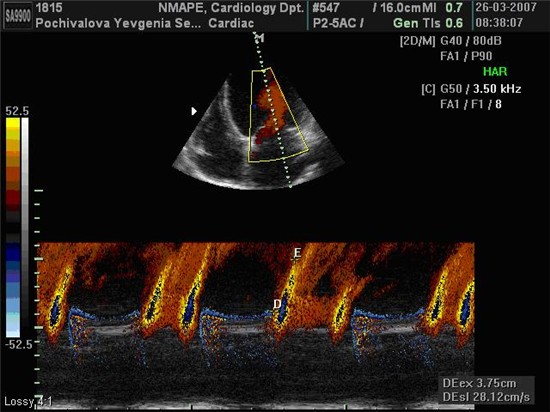

Тканинна допплерографія мітрального кільця

Швидкісні показники руху міокарда ЛШ записувались на рівні кільця мітрального клапану (МК) з використанням імпульсно-хвильової тканинної допплерівської візуалізації (ТДВ) датчиком з фазово-кристалічною решіткою та частотою випромінювання 2.0-4.0 MHz.

Швидкості руху кільця МК визначалися в 4-х позиціях з апікальних 4- та 2-камерного доступів (септальній, латеральній, передній та задній сегменти) з послідовним розрахунком середнього арифметичного значення, що використовувалось для оцінки діастолічної функції ЛШ [Schiller N.B., Recommendations for quantization of the left ventricle by two-dimensional echocardiography / Schiller N.B., Shah P.M., Crawford M., et al.// J. Am. Soc. Echocardiosr. – 1989. – 2. – Р. 358-367.]. При цьому фіксувалися три основні швидкості: пікова систолична швидкість руху МК по направленню до верхівки (S, см/с) та дві пікові негативні діастоличні швидкісті руху МК по направленню до основи сердця в ранню (e’, см/с) та піздню (a’, см/с) фази діастоли та їх співвідношення (e’/a’) (рис. 2.1). Крім того, оцінювали интегральний индекс стану діастолічної функції та тиску наповнення ЛШ – співвідношення швидкості ранньо-діастолічного трансметрального потоку Е до швидкості ранньо-діастолічного руху МК е’ – E/e’ (нормальне значення <8,0 у.о.) [1]. Використовували середні арифметичні значення трьох послідовних циклів. Кольорове картування в М-режимі використовували для розрахунку швидкості розповсюдження діастолічного потоку в порожнині ЛШ (Vp, см/с) (рис. 2.2) та комбінованого показника співвідношення швидкості ранньо-діастолічного потоку Е до Vp (Е/Vp, нормальне значення <1,5 у.о., 1,5-2,5 у.о. – граничне значення, >2,5 – наявна ознака підвищення тиску наповнення ЛШ), що є чутливим предиктором стану діастолічної функції та тиску наповнення ЛШ [Мірошник М. Методика оцінки тиску наповнення лівого шлуночка за допомогою ехокардіографії // Чернігів, ТОВ Санте Інтеграль. – 2006. – 13 С.].

Рис. 2.1 Запис швидкостей руху кільця МК з заднього сегмента у хворого на ІХС з ГХ.

Примітки:

e’ – ранньодіастолічний рух кільця МК.

a’ – пізньодіастолічний рух кільця МК.

S – систолічний рух кільця МК (власне спостереження).

Рис. 2.2 Приклад визначення швидкості розповсюдження діастолічного потоку в порожнині ЛШ за даними кольорового картування в М-режимі.